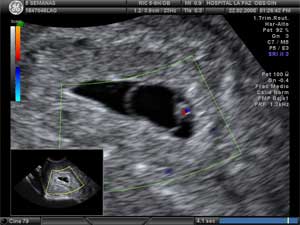

La formación y desarrollo del tubo neural comienza de forma muy temprana en el periodo de desarrollo embrionario. Por ello, estos defectos están determinados desde el comienzo de la gestación, previo al conocimiento de ésta por la madre, ya que el inicio del desarrollo del tubo neural se inicia incluso antes de que a la gestante le haya faltado la primera regla, y termina hacia la semana 6 de embarazo.